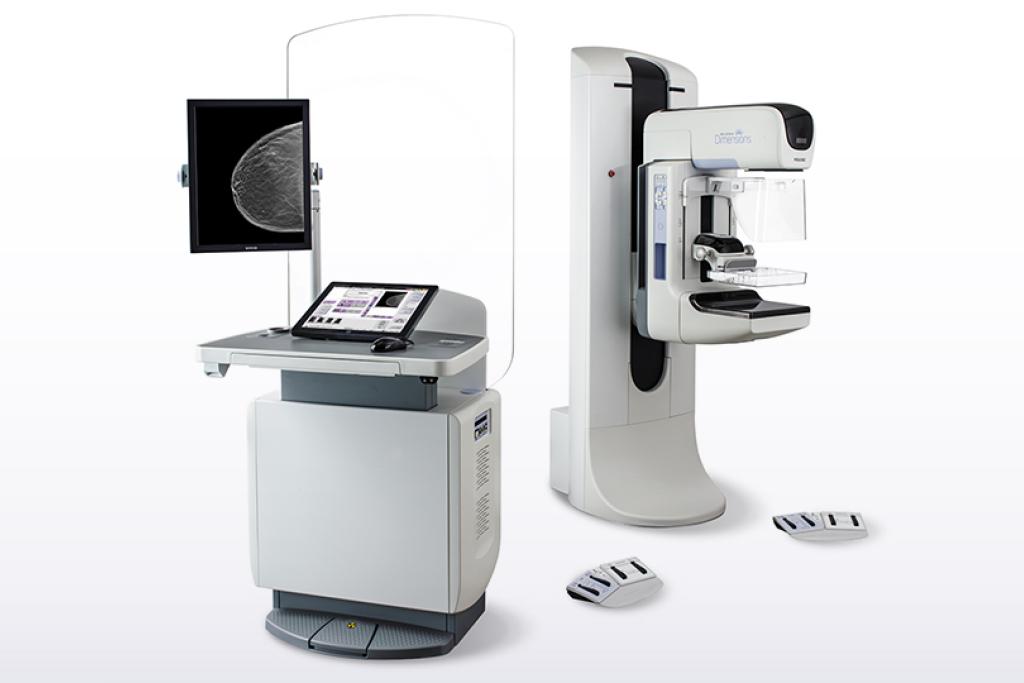

Mammography technology. With the introduction of Selenia Dimensions, we launched the first commercially available system that delivers on the extraordinary promise of breast tomosynthesis.

Selenia Dimensions system's Genius™ 3D Mammography™ exam: Simply a better mammogram.

Hologic has always been at the forefront of breast cancer screening and offers the first breast tomosynthesis technology with proven superior clinical performance to 2D mammography1,4. The revolutionary Selenia Dimensions system, which has set the standard in mammography screening, provides:

The Selenia Dimensions system is available in multiple packages and options to meet your facility's unique needs, all without compromising clinical performance:

The evergreen 2D system that offers the benchmark Hologic customers expect, with essential ergonomics and functional workflow features at an attractive price. Plus, the Selenia Dimensions system 3000 package offers the agility to evolve with you.

The 3D system that offers the benchmark Hologic customers expect, with essential ergonomics and functional workflow features, as well as the Genius 3D Mammography exam, at an attractive price.

The 2D/3D™ system that redefines ergonomics, matched with the perfect balance of enhanced workflow features, taking your performance to the next level.

The premium 2D/3D system that delivers on high performance through its outstanding, optimal ergonomics and elevated, intelligent workflow features that amplify your performance.